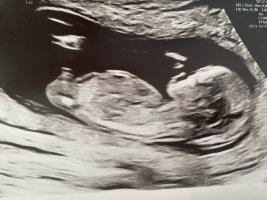

Ikke nub da, men bilde av kjønnet. Hva tenker dere? Han som gjennomførte ultralyden var ganske sikker

Vanskelig vinkel på bildet. Et typisk potty shot er gjerne under rumpa på barnet så det sitter med bena ut til sidene. Her ser det ut som ryggen er med. Kan ikke si jeg kjenner igjen noen av kjønnene her.

Men ser du selv hva jeg har ringet inn på ditt bilde? Det kan ikke være gutt med vagina. Legger ved mitt eget barn som er bekreftet jente 2 ganger. Ser du at det er helt likt som ditt? Dette bilde er tatt i uke 15.